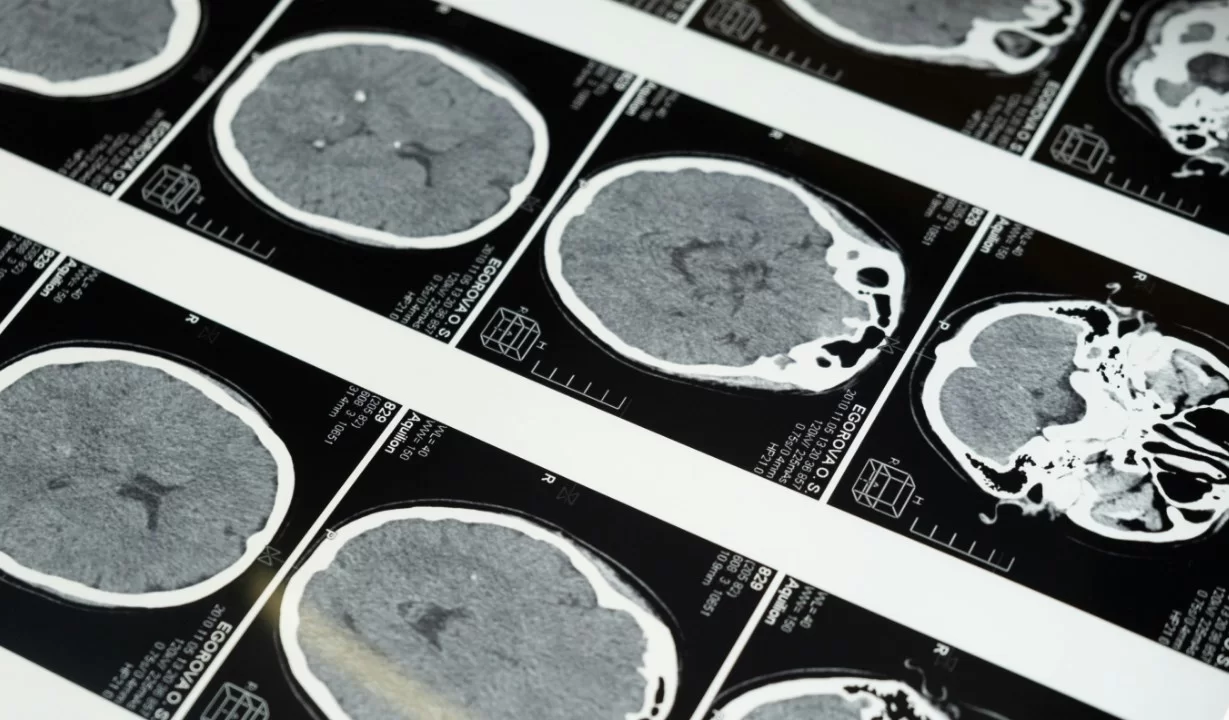

Источник изображения: pexels.com